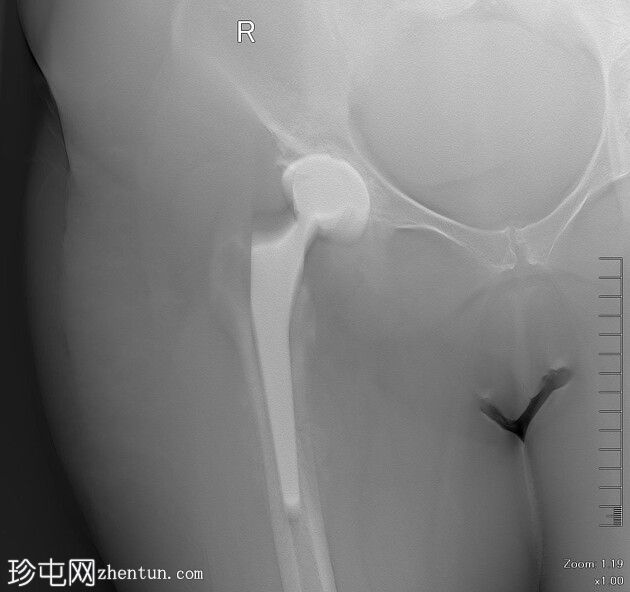

4.jpeg

侧面

在本例中,尽管最初使用抗生素治疗后感染似乎得到缓解,但患者仍出现持续性局部疼痛和慢性骨受累的放射学征象,包括骨膜反应和可能的松动。

这些发现提示慢性骨髓炎,这是一种细菌在骨内持续感染的疾病,通常由于假体等异物的存在和细菌生物膜的形成而加剧。影像学检查中出现的透亮病灶进一步支持了诊断,反映了持续感染导致的骨皮质浸润。